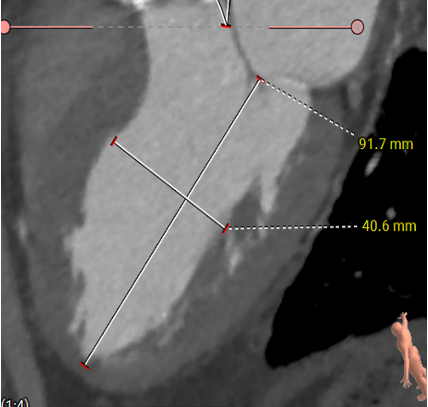

主动脉根部评估

ANNULUS

SOV DIAMETER

LVOT

STJ

ASCENDING AORTA

LEFT VENTRICLE

CT数据显示该患者为Type0主动脉瓣。

主动脉瓣瓣环周长90.3mm,平均周长径 28.7mm,SOV:28.6mm*39.1mm,瓣叶增厚,瓣上钙化分布不均,瓣环水平夹角51°。

冠脉高度测量

LEFT CORONARY

左冠开口高度20.6mm

RIGHT CORONARY

右冠开口高12.6mm